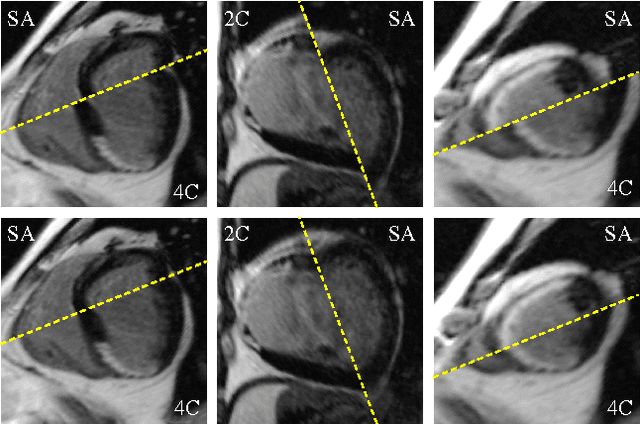

Abstract:Automatic segmentation of the left ventricle (LV) in late gadolinium enhanced (LGE) cardiac MR (CMR) images is difficult due to the intensity heterogeneity arising from accumulation of contrast agent in infarcted myocardium. In this paper, we present a comprehensive framework for automatic 3D segmentation of the LV in LGE CMR images. Given myocardial contours in cine images as a priori knowledge, the framework initially propagates the a priori segmentation from cine to LGE images via 2D translational registration. Two meshes representing respectively endocardial and epicardial surfaces are then constructed with the propagated contours. After construction, the two meshes are deformed towards the myocardial edge points detected in both short-axis and long-axis LGE images in a unified 3D coordinate system. Taking into account the intensity characteristics of the LV in LGE images, we propose a novel parametric model of the LV for consistent myocardial edge points detection regardless of pathological status of the myocardium (infarcted or healthy) and of the type of the LGE images (short-axis or long-axis). We have evaluated the proposed framework with 21 sets of real patient and 4 sets of simulated phantom data. Both distance- and region-based performance metrics confirm the observation that the framework can generate accurate and reliable results for myocardial segmentation of LGE images. We have also tested the robustness of the framework with respect to varied a priori segmentation in both practical and simulated settings. Experimental results show that the proposed framework can greatly compensate variations in the given a priori knowledge and consistently produce accurate segmentations.